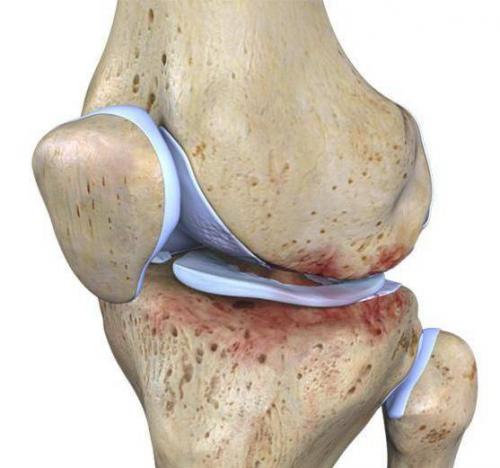

Чтобы лучше понять, почему болят колени, нужно разобраться с их анатомией. Итак, сочленение состоит из бедренной, большой берцовой кости и коленной чашечки. Две самые большие кости имеют по два выступа: внутренний и наружный мыщелки.

Все поверхности, которые соприкасаются друг с другом, покрыты гиалиновым хрящом. Благодаря ему обеспечивается подвижность коленного сустава, его амортизационные свойства. Вокруг этого соединения костей находится своеобразная капсула, изнутри выстланная синовиальным слоем. Она наполнена, благодаря которой производится питание сочленения, обеспечивается его подвижность.

Коленный сустав состоит не только из костей. Все его элементы объединяются крестообразными и коллатеральными связками, бедренными мышцами, сухожилиями. Коленная чашечка крепится к другим элементам посредством собственной связки. Для того чтобы колено двигалось, необходимо 6 синовиальных сумок. Питание и иннервация представленного сустава осуществляется посредством нервов и кровеносных сосудов, которые размещены в мягких тканях, окружающих сустав.